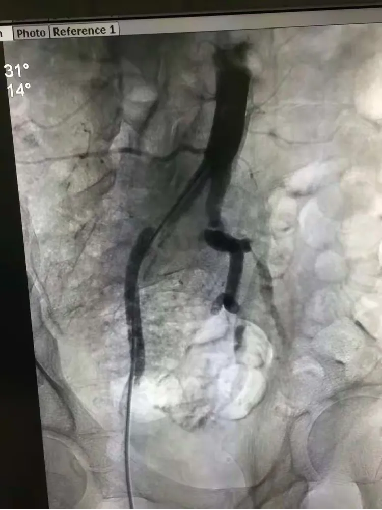

手术中,团队操作沉稳有序:导丝在闭塞血管中精准探路,球囊逐级扩张狭窄段,支架随后稳稳释放。整个过程如行云流水,医护人员配合默契,未见半分忙乱。“血流恢复了!” 监测仪器上跳跃的数据,宣告着双侧“生命线”的重建成功。